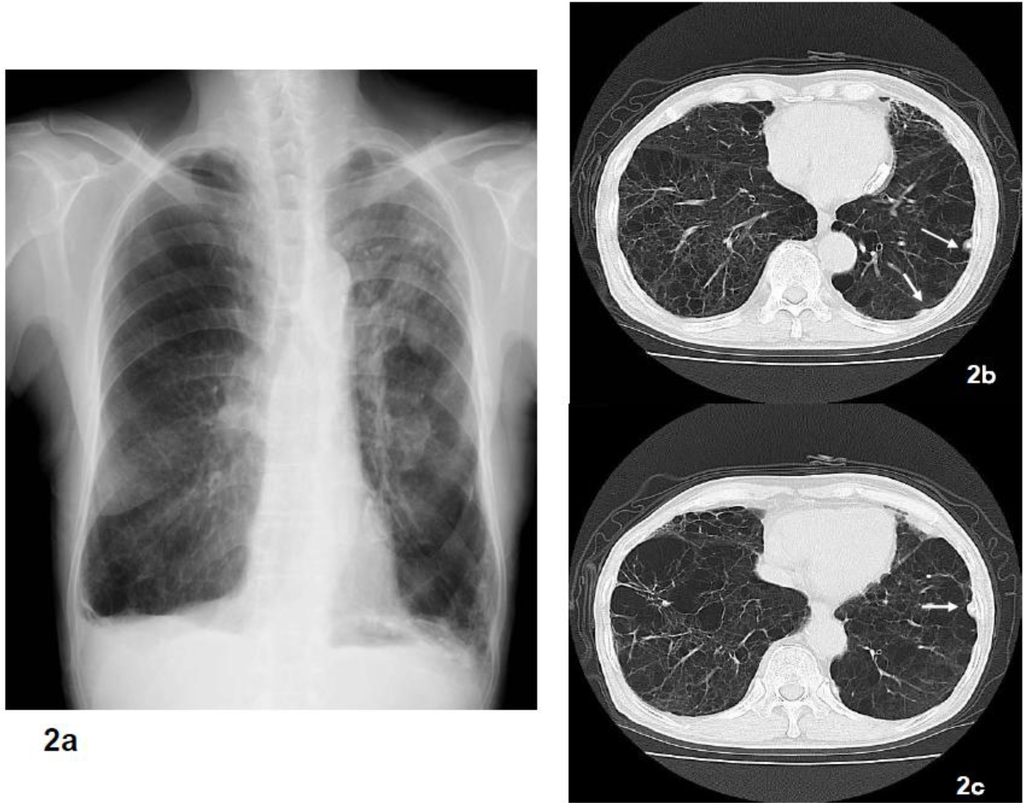

Figure 2.

Although pulmonary emphysema was indicated by radiologically in this case, the pathological findings were characteristic of asbestosis. Pulmonary emphysema was diagnosed based on the chest x-ray (2a), chest CT (2b, 2c) indicated fibrosis accompanied by pulmonary emphysema. However, there were 668,447 asbestos bodies/g in the lungs and histopathologically there were findings of fibrosis of the bronchiole wall and surrounding area accompanying the asbestos bodies.